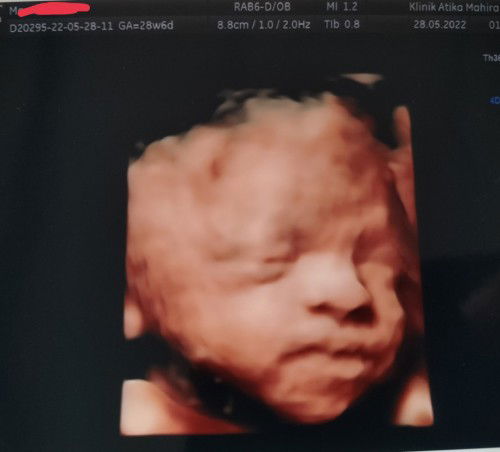

Assalamualaikum... bunda TAP. Pernah berpikir ga kalau SC berulang bisa tidak ya lahiran normal? Alhamdulillah aku masih dikasih kesempatan lahiran normal anak ke 4 setelah 3x SC. Dmn saat SC ke 3 banyak dokter di RS menyarankan langsung steril. Tapi salah satu dokter ini malah mengizinkan aku untuk hamil lg dan mengizinkan lahiran normal setelah 3x SC. Padahal jarak kehamilan kurang dr 24 bln. Alhamdulillah Persalinan normal berlangsung lancar... Proses awal sampai akhir 12 jam. Kadang ketika dunia medis banyak mengatakan "tidak".. ternyata masih ada jalur langit yg meng"iya"kan. Untuk ibu2 hamil yg ingin vbac tetap semangat dan cari nakes yg benar2 dukung sepenuhnya. Berdayakan diri dari awal kehamilan. Noted : toples yg disamping anakku adlh plasentanya. Di tempatku melahirkan pakai metode delayed cord clamping. Penundaan pemotongan tali pusat. Yg fungsinya lumayan baik untuk bayi. #vbac #vba2c #vba3c